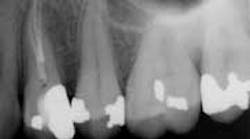

The success of endodontic treatment is directly related to the clinician’s ability to remove maximum numbers of bacteria from the root canal system. (1,2) If we can agree that all root canal treatment is associated with a certain degree of skill and precision in spite of perceived ease of treatment, I think it is fair to say there are no easy root canals. Some teeth are more difficult than others due to access limitations or anatomy, but the problem that faces all of us, in every tooth, is our inability to measure the absence of bacteria within the root canal and the potential for microanatomy to exist at any level of the root—whether it is a five-canal molar or a single-rooted anterior. It is impossible to determine the exact terminus of the root canal system, and there is no uniform agreement about where the root canal system ends. (3,4) The use of an apex locator can aid in this determination, but there is often disagreement between radiographic information and an apex locator, even in single-rooted anterior teeth, because the canal terminus can be at the radiographic apex or as much as 3 mm from it. (5) All instrumentation techniques leave a certain amount of the canal wall untouched, and we are not able to sterilize the root canal system. (6,7) The apical portion of any tooth may have dentinal tubules that can harbor bacteria, and the concept of a single uniform canal opening at the apex is anything but accurate. (8,9) Many teeth will have multiple portals of exit that may or may not be present in the apical third of the root. (Figure 1) As a result, the clinician must assume the apical canal anatomy in every tooth is highly variable in size, shape, and number (10,11,12) and there are no “easy ones.”

maxillary central incisor with a necrotic pulp. A prominent lateral canal can be seen,

but there is no way to know if multiple microscopic branches are present at any level

of the root canal system.